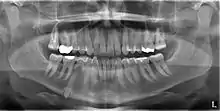

Classifications enable the oral surgeon to determine the difficulty in removal of the impacted tooth. [9] The primary factor determining the difficulty is accessibility, which is determined by adjacent teeth or other structures that impair access or delivery pathway. The majority of classification schemes are based on analysis on a radiograph. The most frequently considered factors are discussed below.

Angulation of tooth

Most commonly used classification system with respect to treatment planning. Depending on the angulation the tooth might be classified as:

Relationship of tooth to anterior border of ramus

This type of classification is based on the amount of impacted tooth that is covered with the mandibular ramus. It is known as the Pell and Gregory classification, classes 1, 2, and 3.[10]

Relationship of tooth to occlusal plane

The depth of the impacted tooth in relation to the adjacent second molar serves as the foundation for this type of classification. This was also given by Pell and Gregory and is known as the Pell and Gregory A, B, and C classification. Relationship to the occlusal plane A-C classes